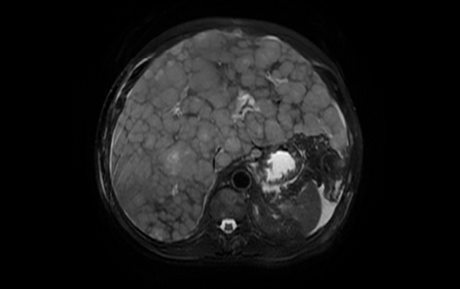

53 year old Caucasian male presented with non-productive cough and orthopnea since 7 days, abdominal discomfort - localized to right lower quadrant, followed by abdominal distention and yellowing of eyes and urine since 4 days. Consumed 50 tablets of Tylenol to relieve abdominal pain. His past medical history was relevant for end stage COPD, he was a current smoker with 15 pack year smoking history, and consumed 10-15 beers per week. Family history relevant for liver disease of unknown etiology in his mother. Social history 15 pack year smoking history drinks 10-15 beers per week. Physical examination relevant for evidence of facial wasting, citric sclera, distended abdomen with fullness in RUQ. Admission labs significant for mild uremia BUN/Cr 47/0.5 , bicarbonate 22, anion gap 17, AST/ALT 689/403, amylase 32, alkaline phosphatase 1018, lipase 218, ammonia 113, ethanol<10, bilirubin 5.8 , salicylate<1, lactate 4.3, Tylenol < 10, ABG -7.36/42/83/23.6/96% 2l nasal cannula. Chest x-ray showed evidence of increased fullness of left hilum and Ct abdomen showed heterogeneously enhancing nodular enlarged liver with small as cites and enlarged lymph nodes in Porto hepatic region related to hepatic cirrhosis vs a diffuse infiltrating neoplastic process.1

CT abdomen

Figure 2

Figure 2 CT abdomen.